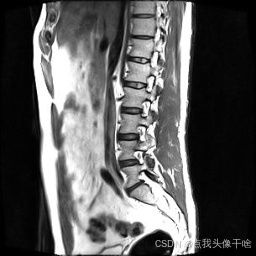

想象一下,你给AI看一张脊椎的核磁共振(MRI)照片,它就能像经验丰富的医生一样,把照片里每一块骨头、每一节椎间盘都给你清清楚楚地标记出来。这个系统干的就是这个酷炫的事儿!

- 原图:就是一张张脊椎的MRI扫描图。